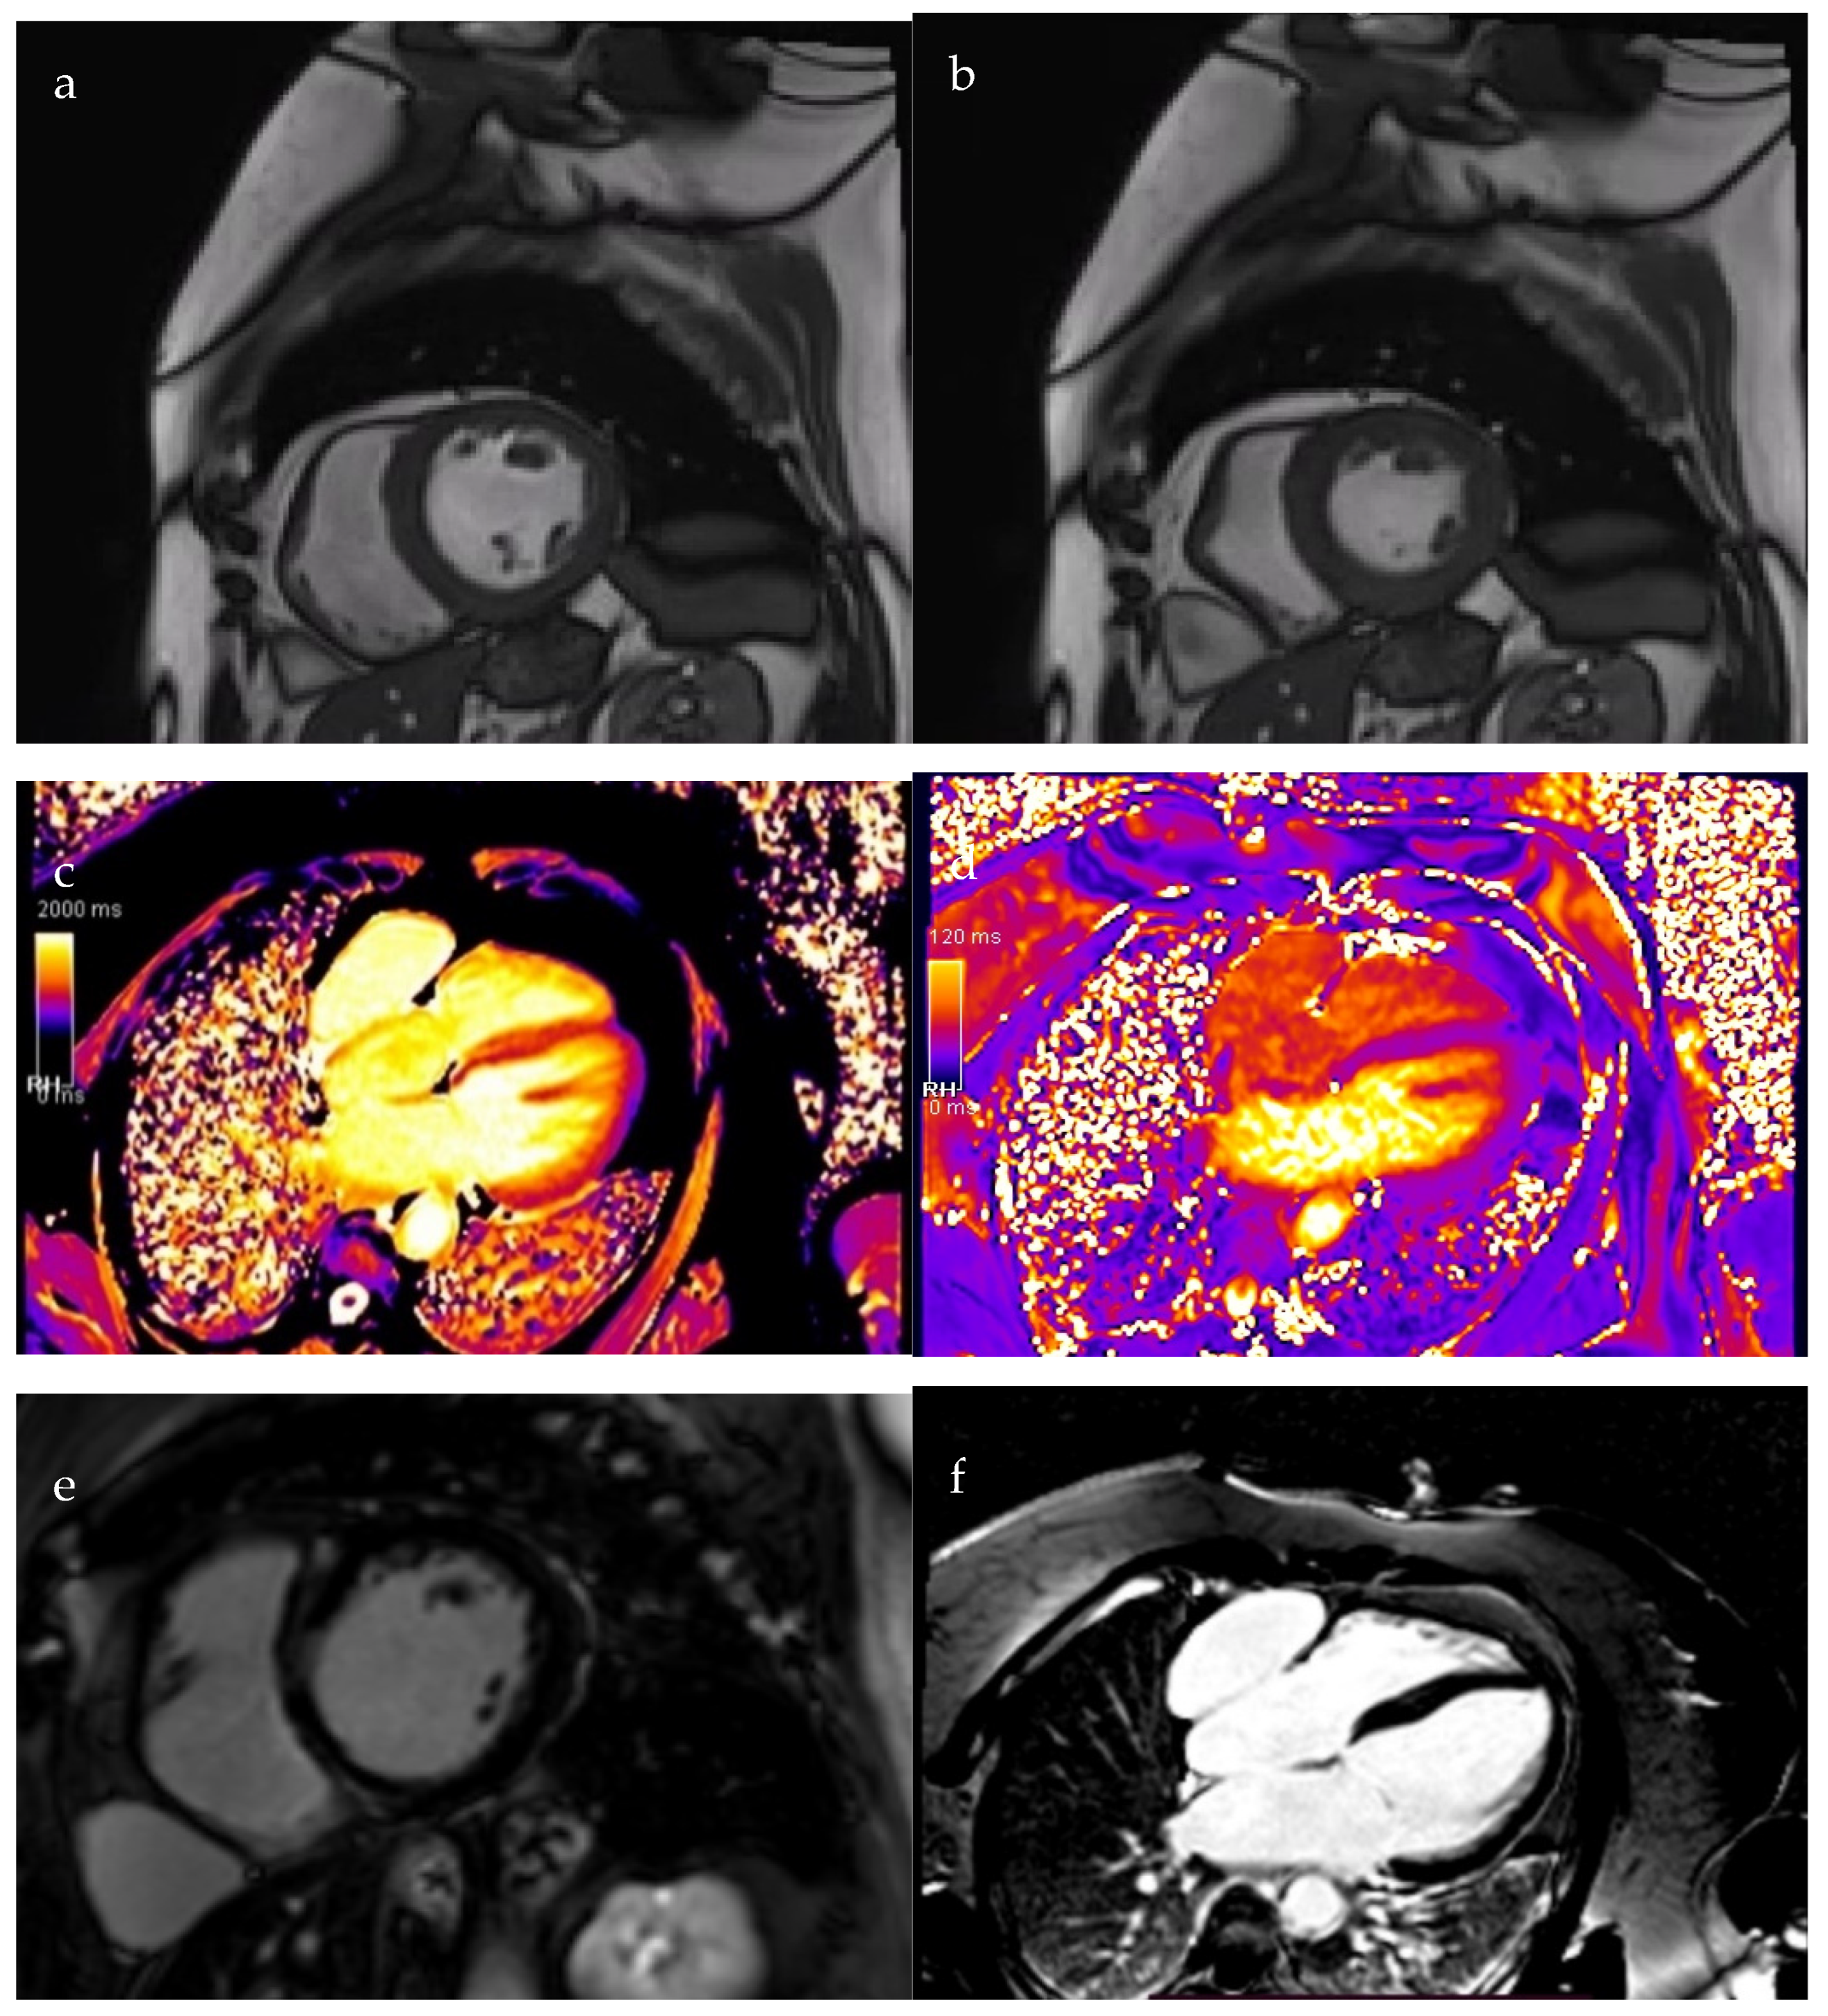

Two months post-discharge, cardiac MRI demonstrated a notable improvement in left ventricular systolic function, with the ejection fraction increasing to 42%, though hypokinesia persisted in the interventricular septum. Early T1 mapping demonstrated a mildly increased signal in the interventricular septum, while T2-weighted imaging was unremarkable. Late gadolinium enhancement (LGE) sequences revealed a non-ischemic, mid-myocardial pattern of contrast uptake involving the interventricular septum and right ventricular insertion points, findings consistent with chronic myocarditis.

Additionally, MRI identified a well-defined, intrapericardial pouch measuring approximately 20 cm2, located anterior to the right atrium, with a 15 mm communication to the atrial cavity, suggestive of a right atrial diverticulum (Figure 3).

Figure 3.

Cardiac MRI. (a). Diastolic view; (b). Systolic view; (c). Early T1 acquisition; (d). T2 acquisition; (e,f). LGE sequences: mid-myocardial contrast uptake with non-ischemic pattern at the interventricular septum and right ventricular insertion junction; (g,h). Right atrium diverticulum (red arrow).